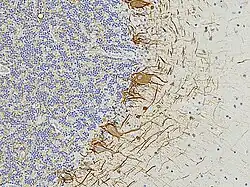

EnCor has always collaborated with basic scientists and clinicians to produce articles in peer-reviewed scientific publications focused on the examination of various plasma, serum and CSF biomarkers of nervous system damage and degeneration. One of these is the phosphorylated, axonal form of the major neurofilament protein heavy chain protein which has the HGNC name NEFH,[3][4][5][6] though is usually referred to as pNF-H in the scientific literature. Two further studies describe novel EnCor assays for UCHL1[7] and alpha-synuclein,[8] two major brain proteins implicated in the development of Parkinson's and other neurological diseases. In 2022 EnCor, in collaboration with researchers at the University of Florida described a novel class of antibodies to neurofilament light chain with the HGNC name NEFL, although the protein is usually referred to as NF-L. Surprisingly, one class of these antibodies bind epitopes hidden in healthy neurons and their processes but which are revealed on degeneration. Another class of antibody to neurofilament NF-L was shown to bind only neurofilaments in healthy neurons and their processes but failed to recognize degenerating and degenerated neurons and processes.[9] The antibodies degeneration specific antibodies have been dubbed "DegenoTag" reagents and should have wide utility for researchers on neurodegeneration. By 2022, the EnCor product line had increased to over 250 items, the antibodies mostly being used for research purposes, with a particular focus on immunocytochemistry and western blotting, though many are also utilized for immunocytochemistry, immunoprecipitation and ELISA. Some have become useful for diagnostic histopathology and for monitoring the levels of protein biomarkers, of research and potential clinical utility. EnCor supplies reagents to research labs and other reagent companies such as Abcam, BioLegend, Thermo Fisher Scientific, EMD Millipore, and Bio-Techne. EnCor is well known for the quality of its cell, tissue and western blotting images, many of which have been made available on Wikipedia Commons and widely used in books, articles, posters, for teaching, advertising and many other purposes, see [1].